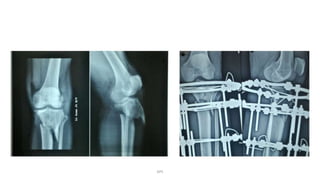

Nonunion

DPS